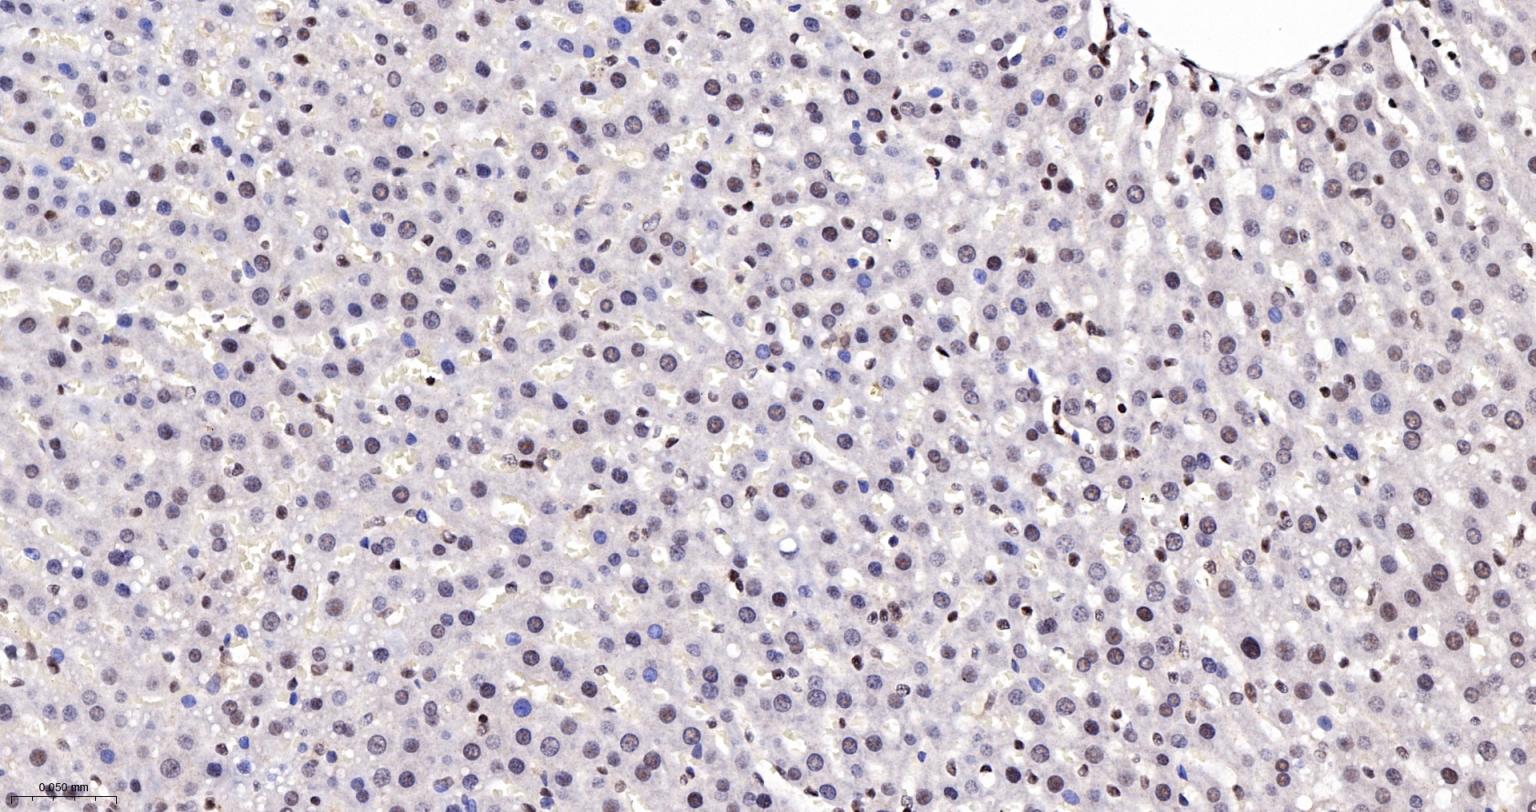

Paraformaldehyde-fixed, paraffin embedded Rat Liver; Antigen retrieval by boiling in sodium citrate buffer (pH6.0) for 15 min; The section was incubated with CTCF Monoclonal Antibody, Unconjugated (bsm-61422R) at 1:200 overnight at 4°C, followed by conjugation to the bs-0295G-HRP and DAB (C-0010) staining.